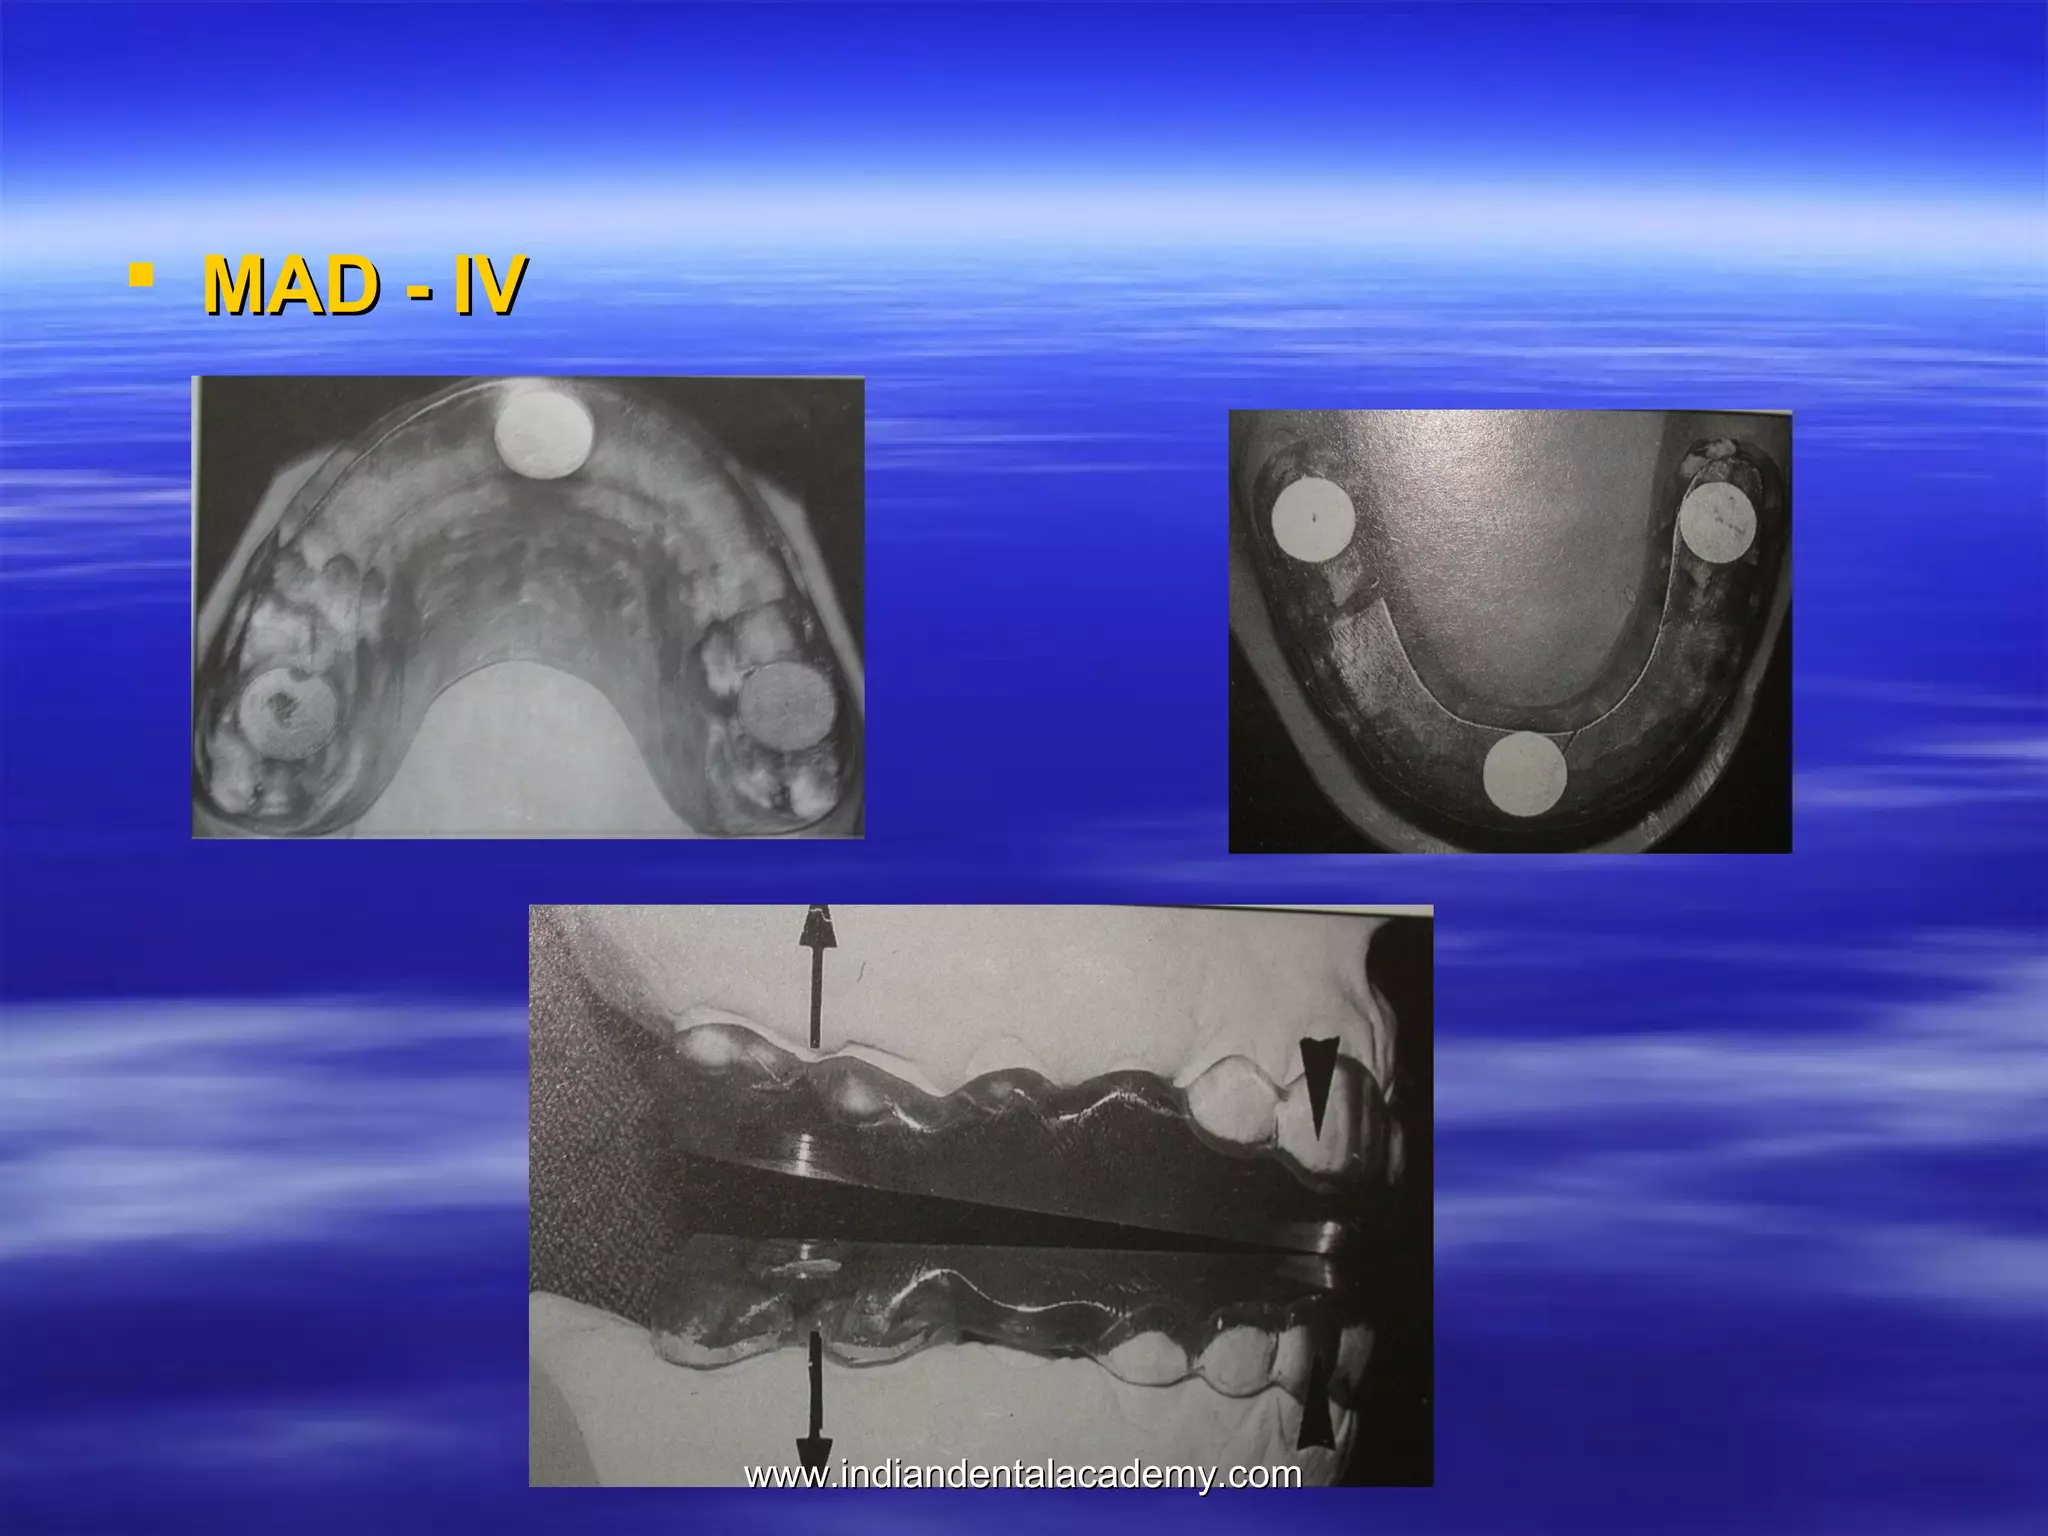

 MAD - IV

www.indiandentalacademy.com

MAD IV(a)

MAD IV( b)

MAD IV( c)